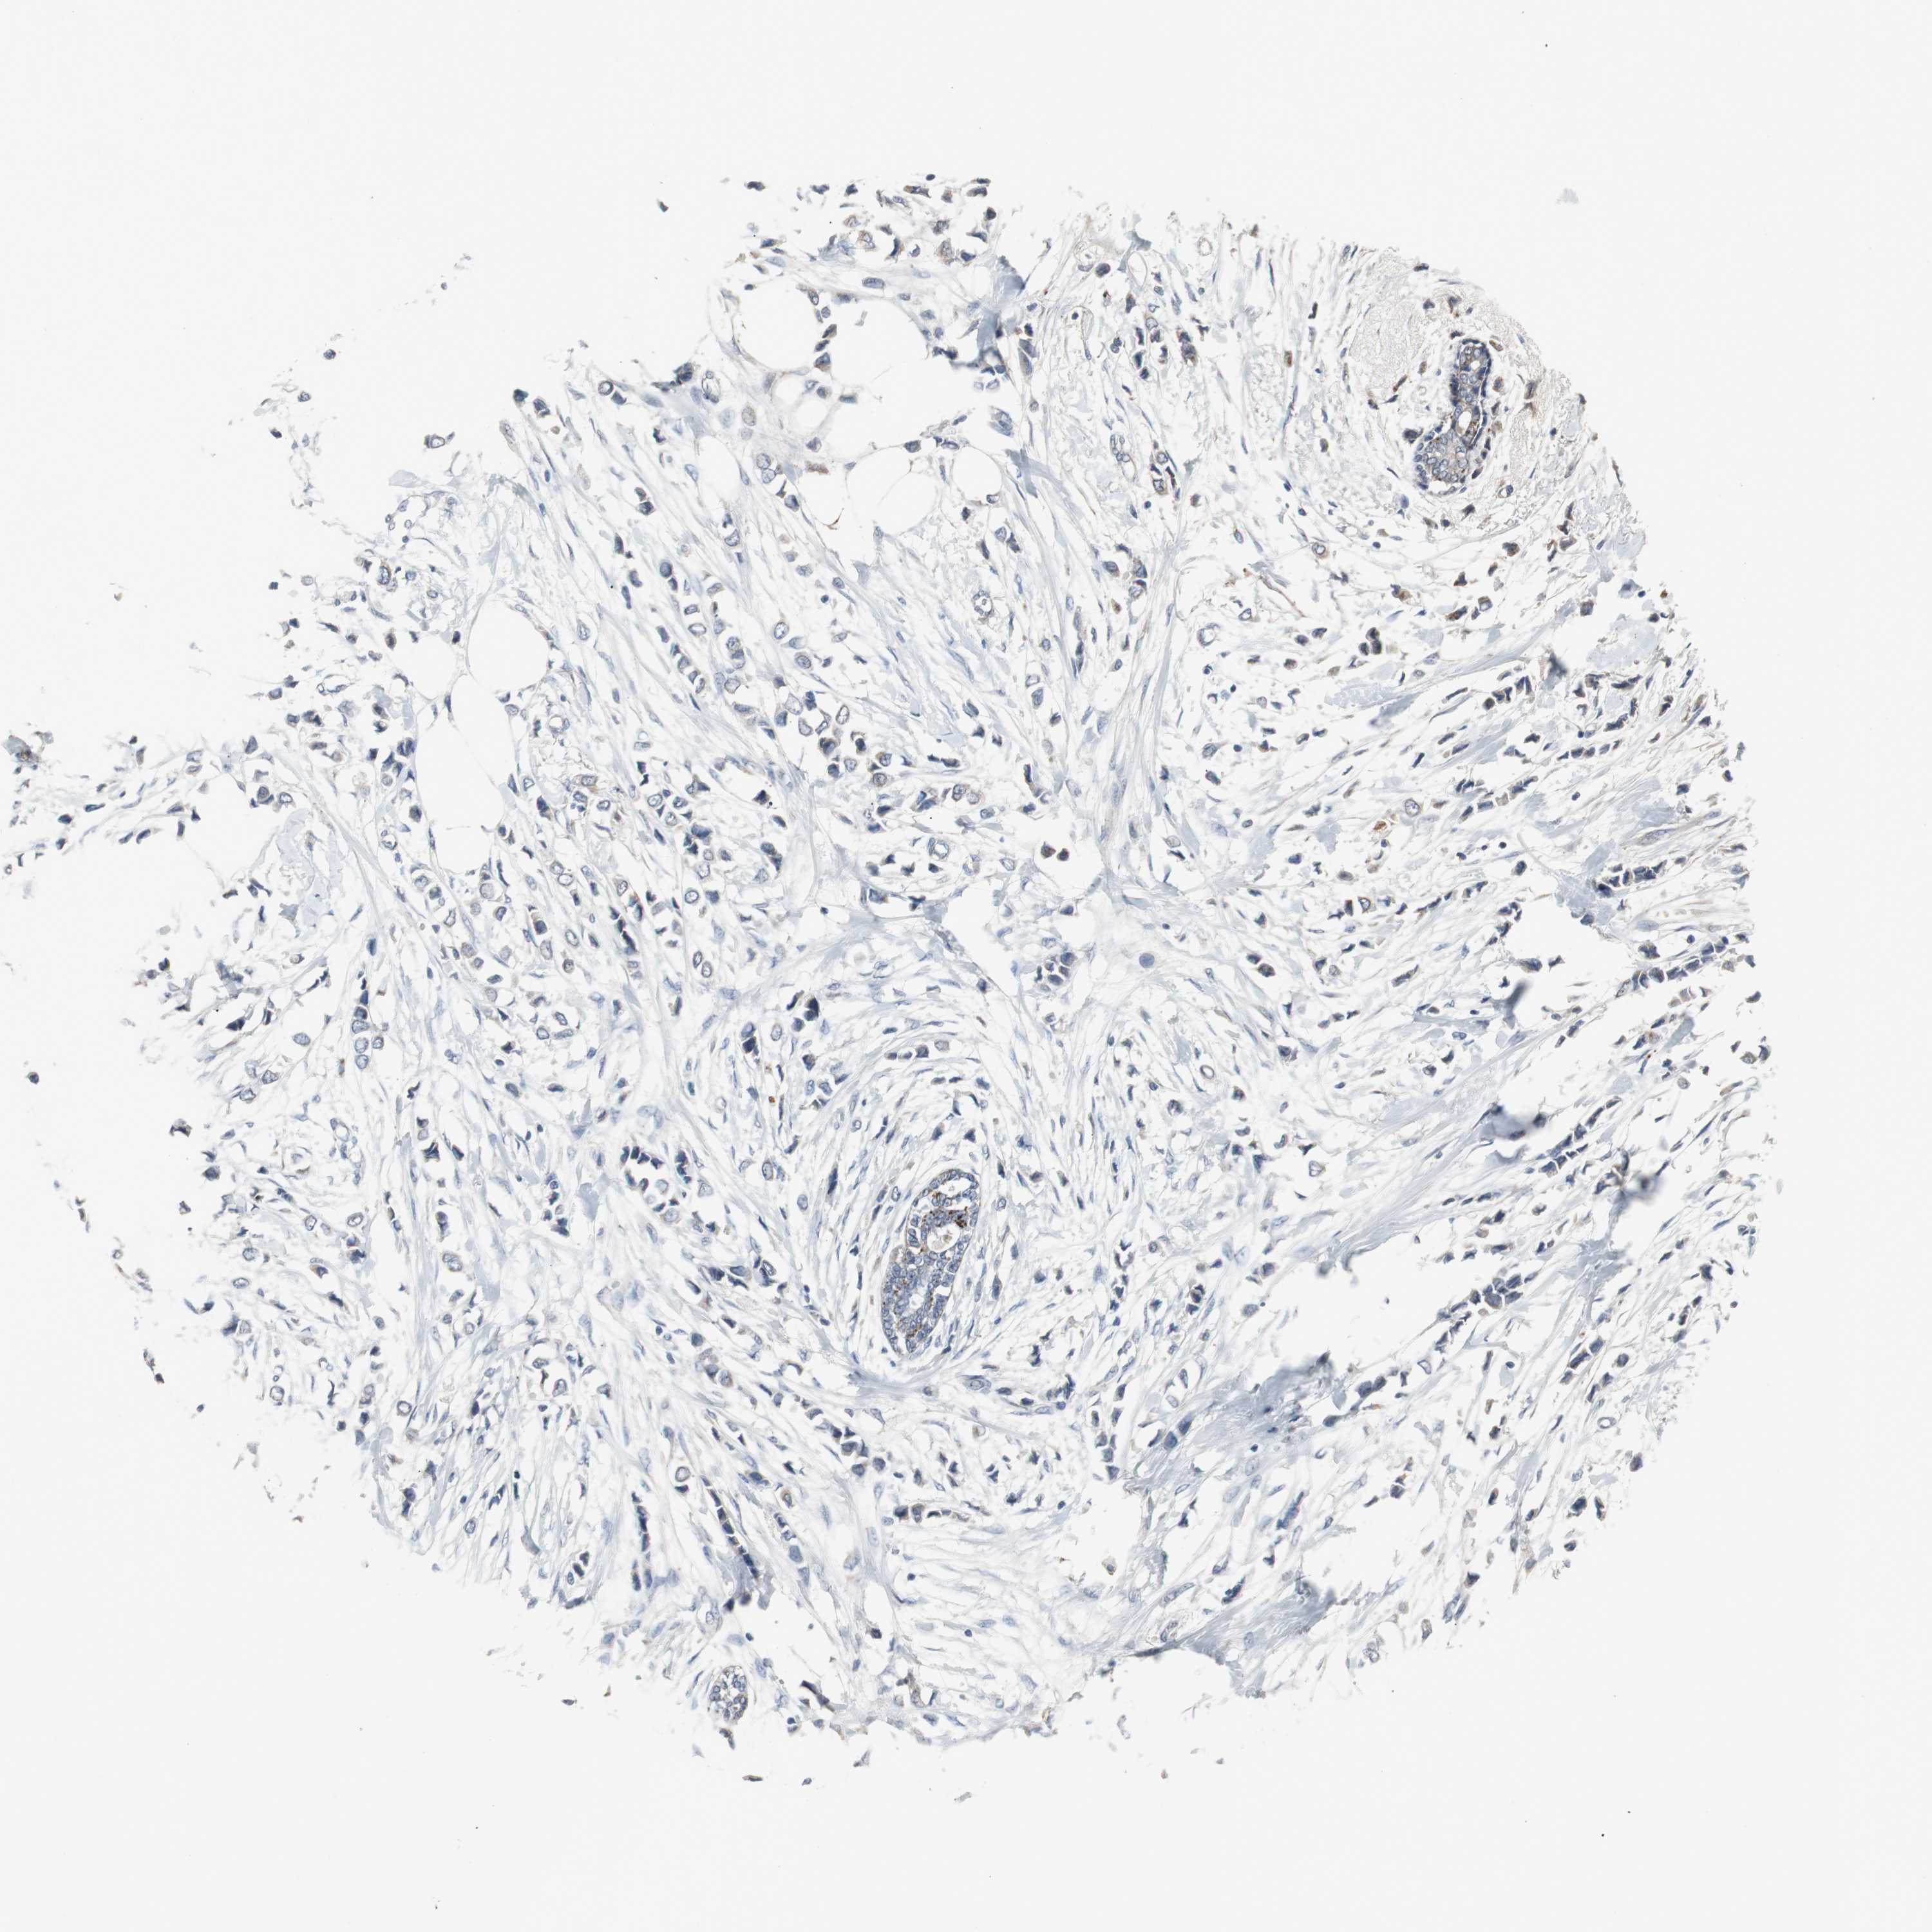

BRCA TCGA BRCA VALIDATION PROTEIN EXPRESSION

ANTIBODIES

AND

VALIDATION